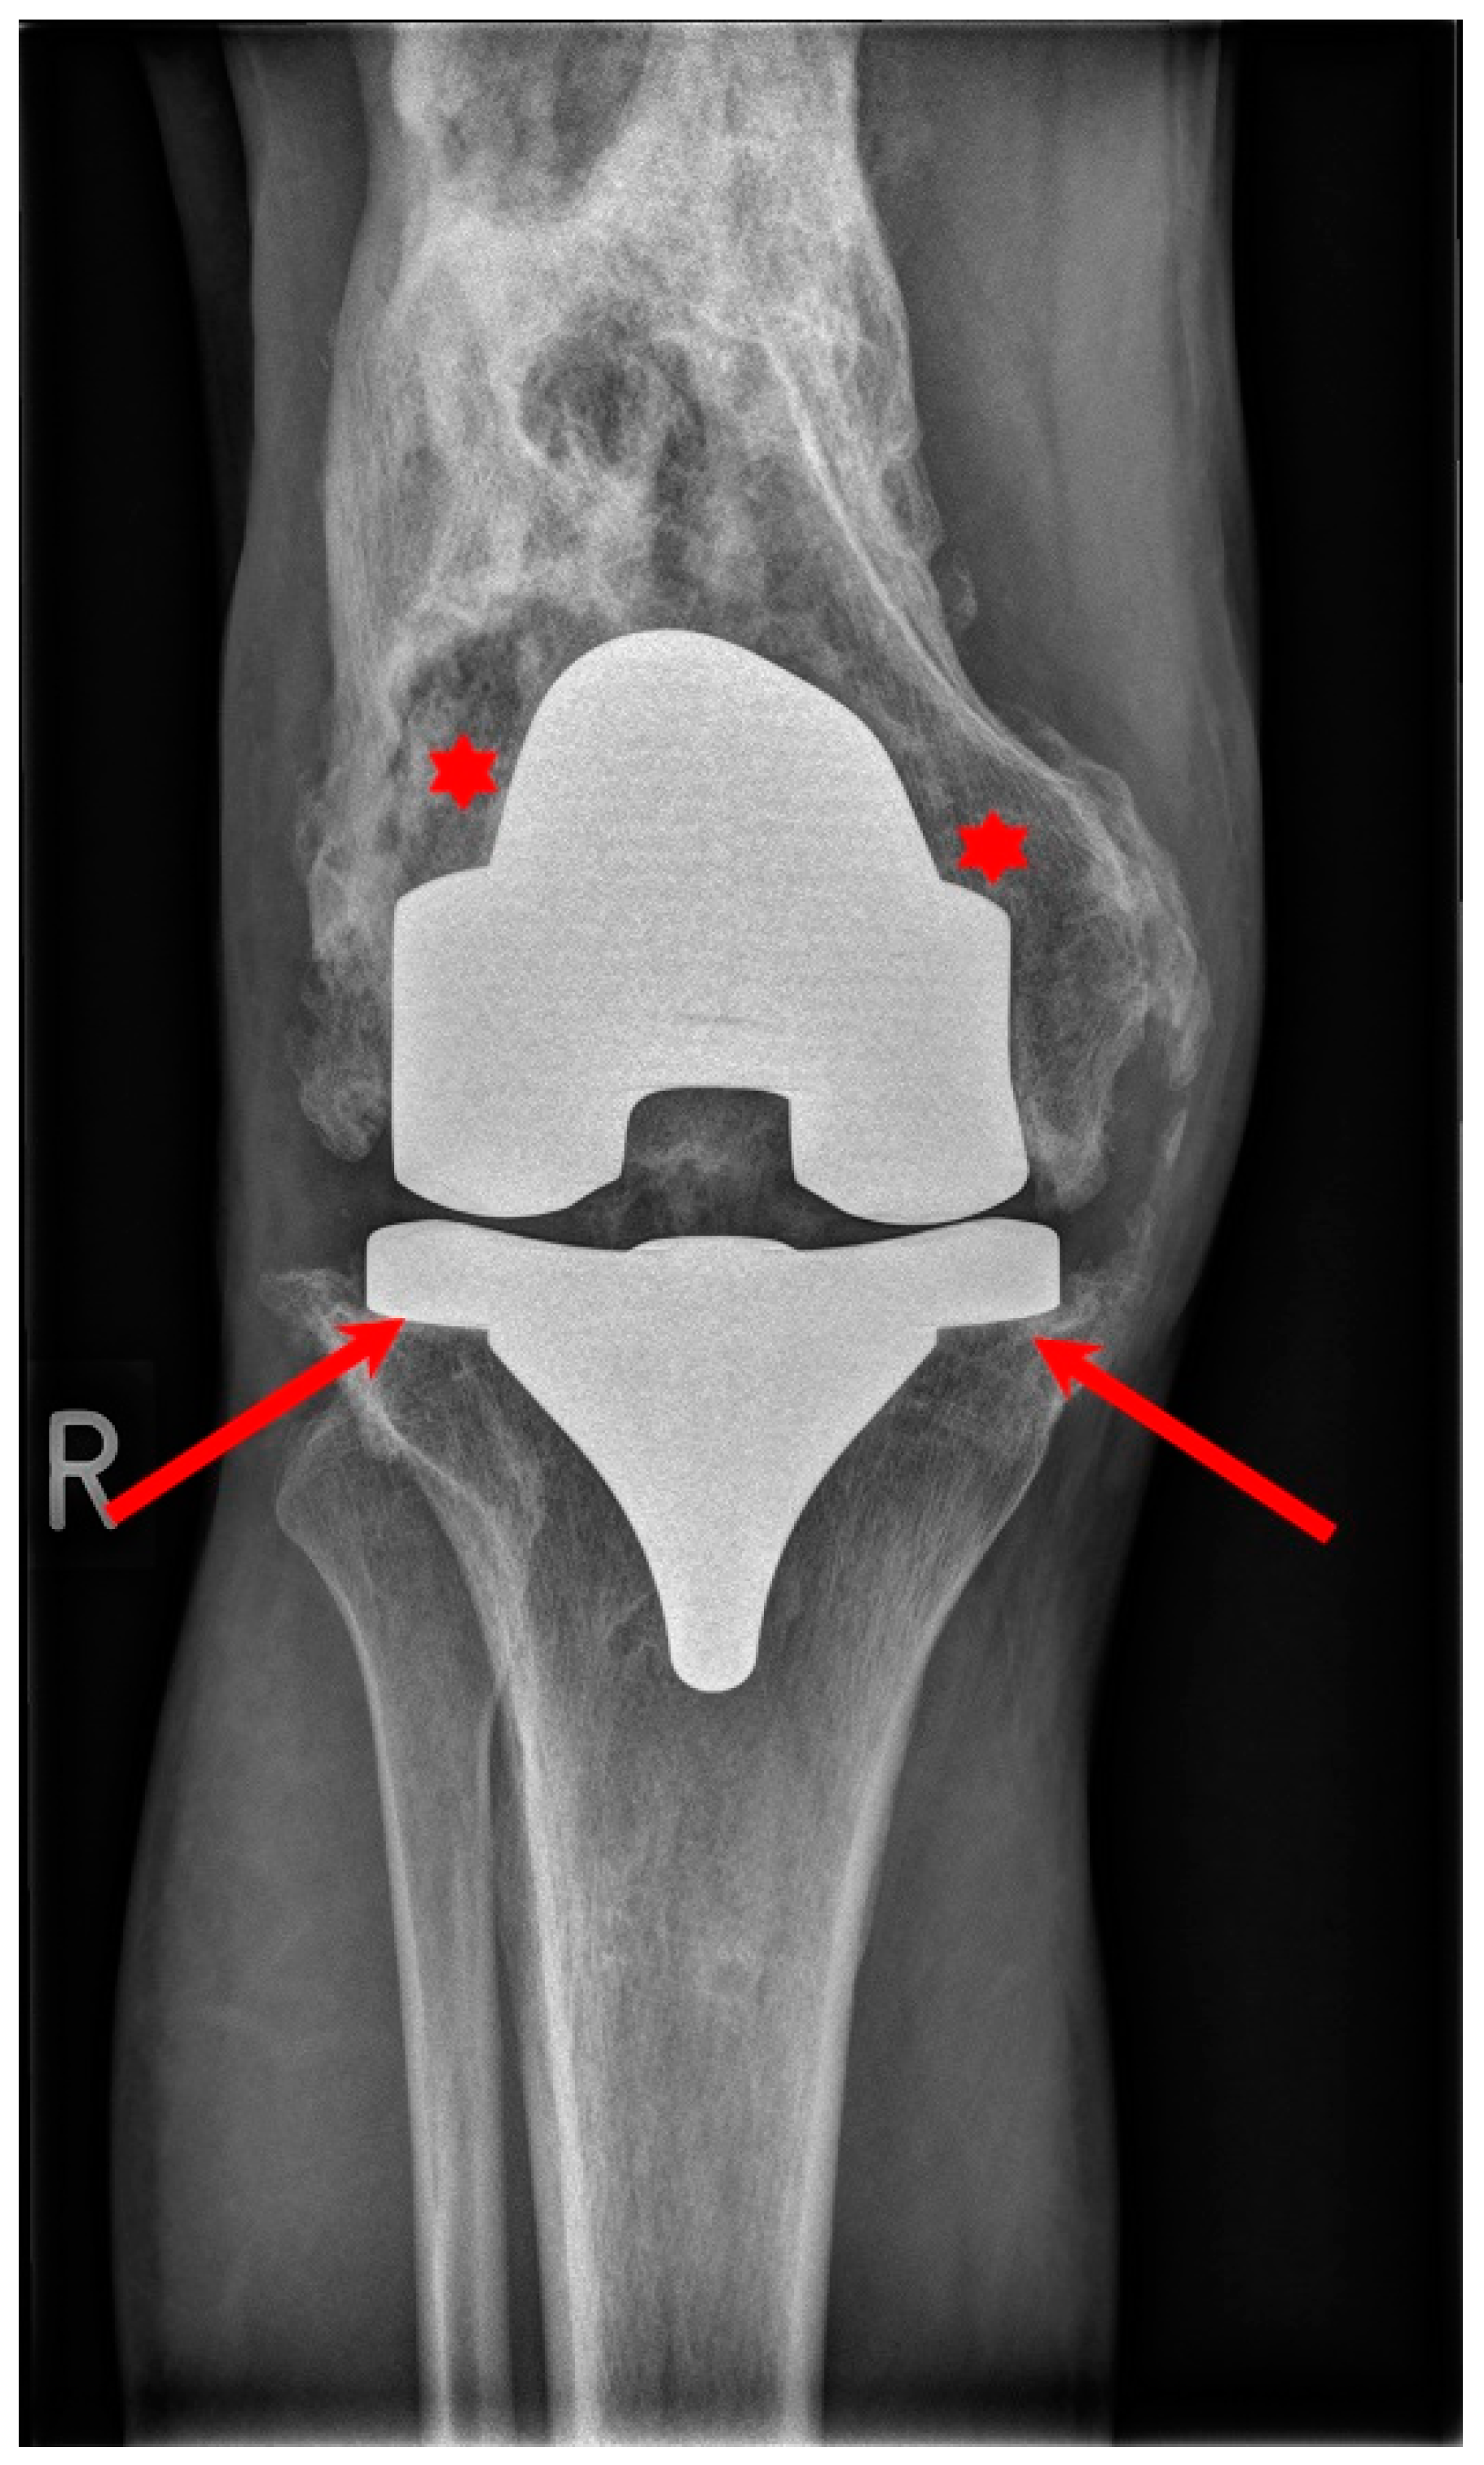

The use of cement in a TKA requires appropriate prepping, careful application of the cement and removal of excess cement with thorough washing prior to closing. This process adds extra time to the surgery duration and removes natural growth factors, which are important for fast adaptation and fixation of the implanted prothesis. Since a cementless TKA relies on the biological bond between the bone and the implant, this process may be skipped, thus, the length of the procedure is shorter. As longer operative times are associated with a greater chance of postoperative infection, there is a possibility to add an antibiotic into the cement and prevent periprosthetic infection, which is a debilitating complication that can be observed in Figure 4. Furthermore, cemented fixation is technically problematic when revision is needed, making reoperation impossible in some particular cases [48]. During this procedure, cement used in the primary total knee replacement has to be removed, as well as the protheses components themselves. Removing this cement from the bone is a time-consuming process that adds extra time to the length of the surgery. After this, the bone surfaces must be prepared for the revision implant. In some cases, there may be significant bone loss around the knee. If this occurs, metal augments and platform blocks could be necessary to add to the main components in order to provide suitable fixation. Sometimes bone graft materials can be used as well.

Figure 4.

Conventional X-ray showing septic loosening of the TKR with bone destruction (asterisk) and loosening of the implants (arrows).